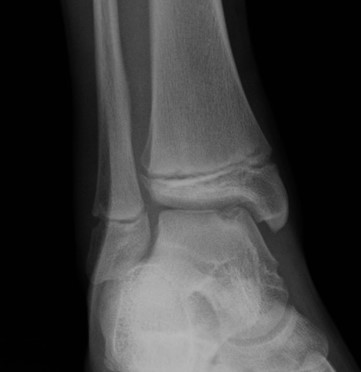

Fugengelenkfrakturen treten typischerweise vor dem 10. Lebensjahr auf, in einer Phase, in welcher die Wachstumsfugen noch weit offen sind. Dieser Frakturtyp betrifft fast ausschließlich den medialen Malleolus. Laterale Frakturen sind extrem selten, teilweise kommt es zu lateralen Bandverletzungen oder Fugenschaftfrakturen der distalen Fibula. Die Frakturlinie verläuft in einer Verlängerungslinie von der medialen Taluskante nach proximal. Häufig stellen sich Verletzungen des Innenknöchels im Röntgenbild schlechter dar, insbesondere wenn die Aufnahmen verdreht sind oder die Ebene der Fraktur bei geringer Dislokation verkippt zur Röntgenebene liegt. Besteht klinisch der geringste Hinweis auf eine Verletzung des Innenknöchels, muss aufgrund der Tragweite der Verletzung durch entsprechende Aufnahmen gegebenenfalls auch Schnittbildverfahren die Verletzung sicher diagnostiziert oder ausgeschlossen werden (Abb. 15).